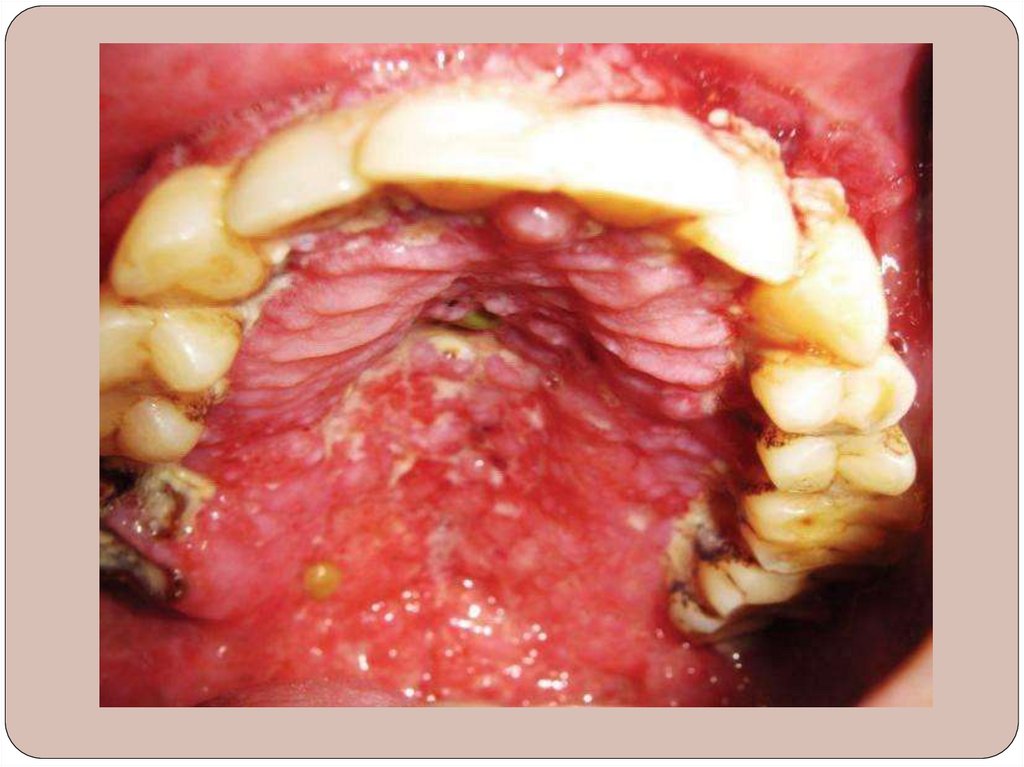

Милиарно-язвенный туберкулез – встречается

редко.

Возникает у больных, страдающих тяжелыми

формами туберкулеза легких или гортани,

сопровождающихся выделением с мокротой

большого количества микобактерии туберкулеза.

Поражаются главным образом постоянно

травмируемые участки слизистой оболочки щек по

линии смыкания зубов, спинка и боковые

поверхности языка, мягкое небо, дно полости рта.

В местах травм появляются серовато-желтые или

красноватые точечные (несколько возвышающиеся

над СО) образования, которые быстро распадаются

с образованием язв.